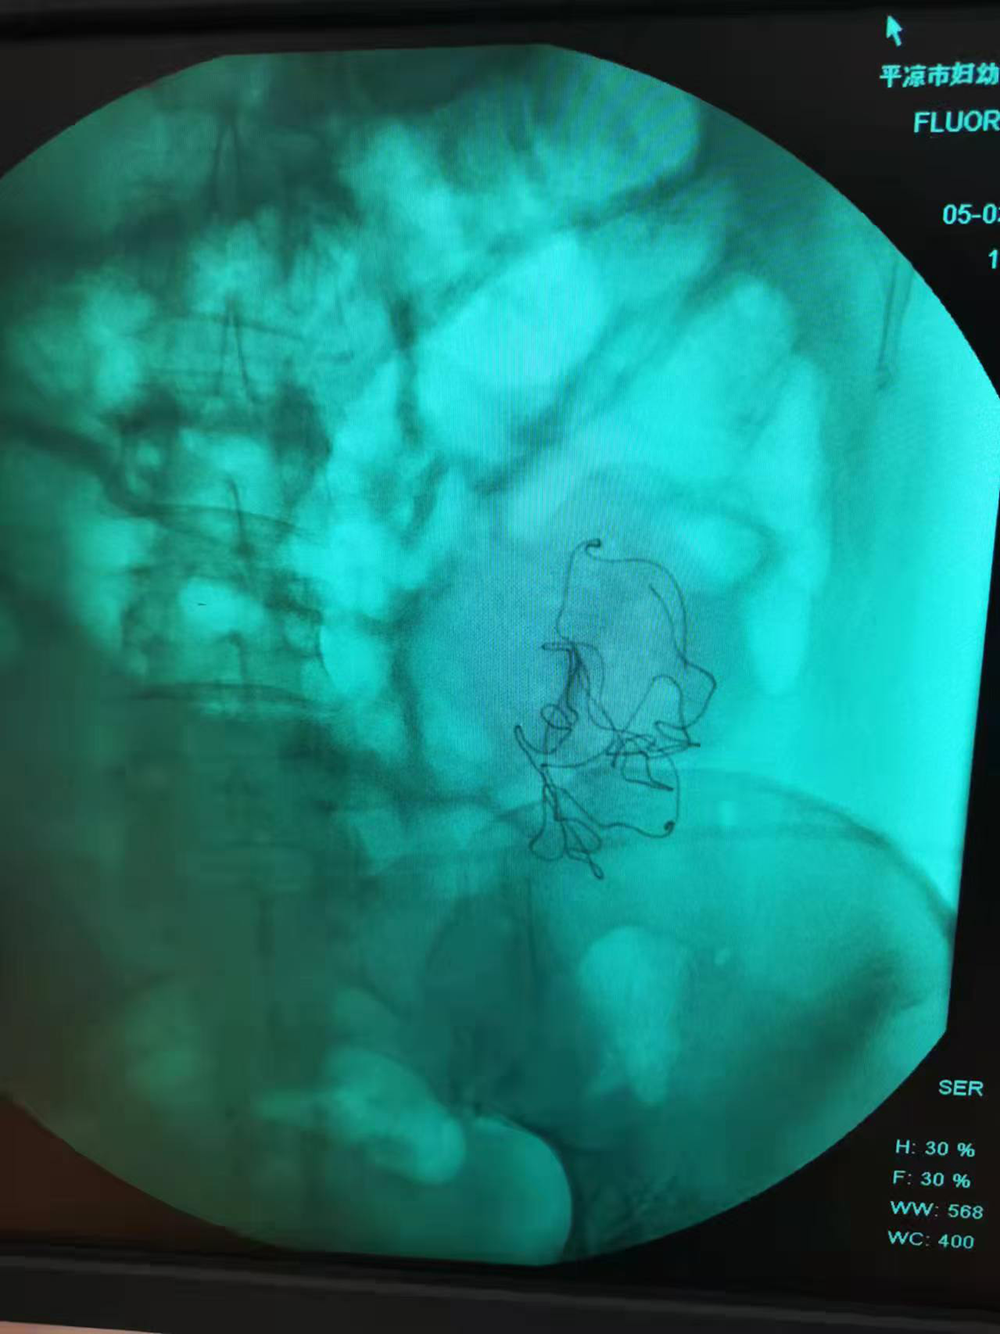

在秦红利多次请求下,院方终于将当时的检查影像交给了她。影像中,腹腔内异物影清晰可见。然而,在当天的手术记录中,这一异常没有留下任何痕迹。

秦红利分娩后,进行X光检查发现异物清晰可见。本文图片均为受访者供图